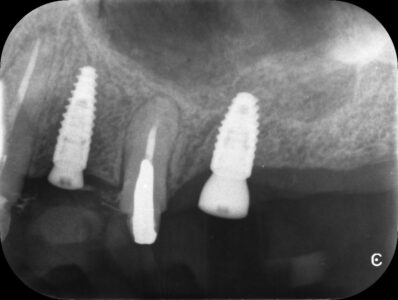

Planificación de Implantes: Precisión milimétrica

Máxima precisión en implantes dentales: Planificación con tecnología 3D

Planificación digital de implantes: La tecnología al servicio de tu sonrisa